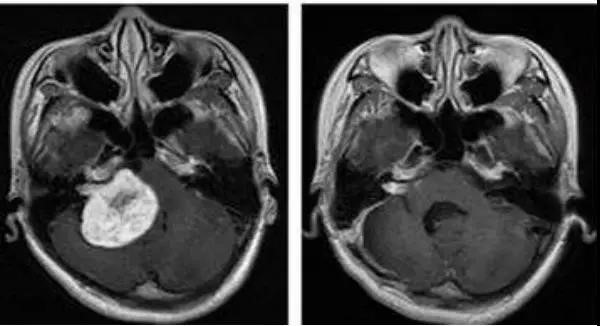

质子治疗的效果如何?

国际上公认质子治疗是对实体肿瘤最精密和最准确的放疗方法之一,并在临床肿瘤治疗应用中显示出独特的优越性。